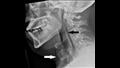

وكشفت الأشعة السينية أنه يعاني من انتفاخ الرئة الجراحي، عندما ينحصر الهواء في أعمق الأنسجة تحت الجلد.

وأظهرت الأشعة المقطعية أن التمزق كان بين العظمتين الثالثة والرابعة من رقبته وأن الهواء يتراكم في الفراغ بين الرئتين في صدره.